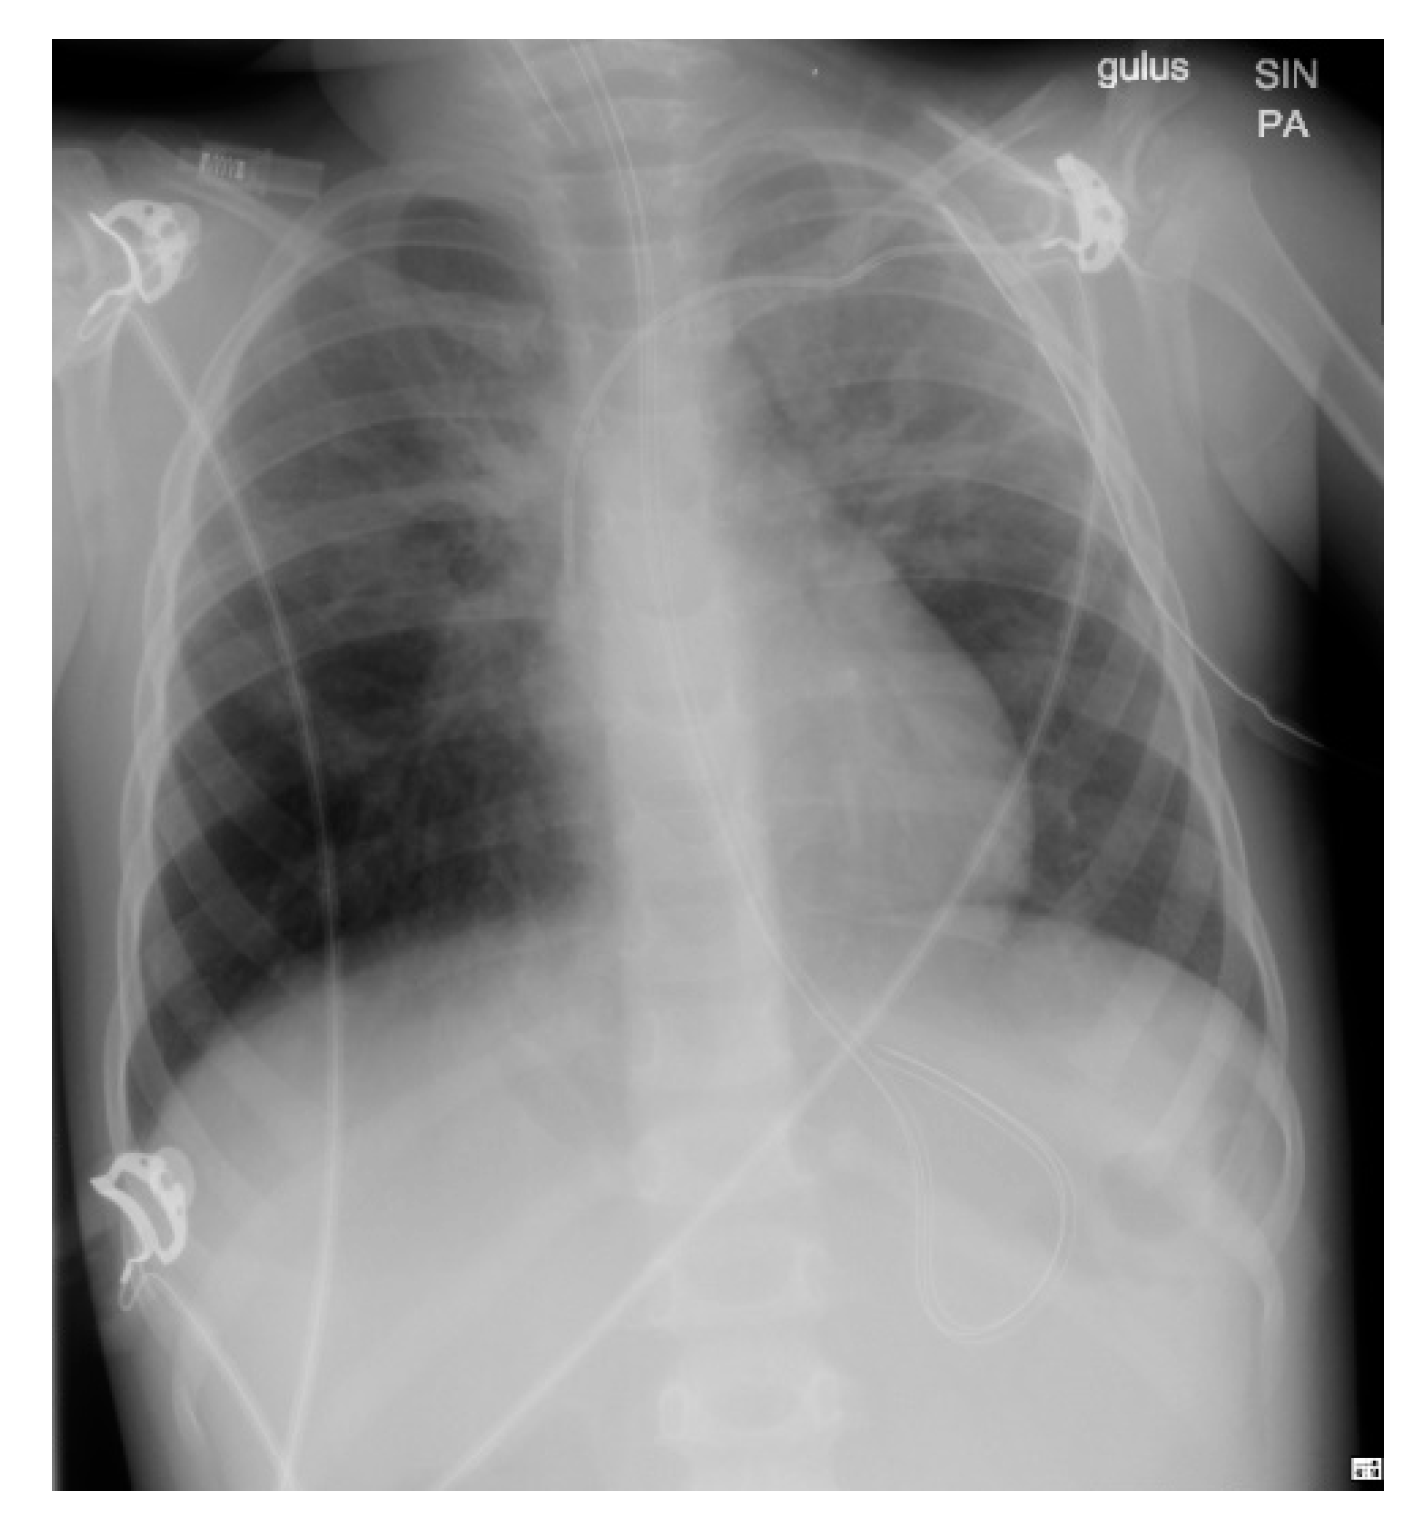

Following the measures taken, the patient’s condition improved with increasing SpO2% levels, resolving respiratory failure on CBG, and gradually clearing signs of pneumonia on the chest X-ray. To prevent respiratory alkalosis, ventilation was switched to CPAP at this point and later on, the patient was extubated.

Following extubation, the patient’s breathing rate was normal at ~16/min. Initially, the patient required oxygen support to maintain SpO2% levels but was gradually weaned off until it was no longer required. A chest X-ray obtained at this stage (Figure 3) demonstrated resolving pneumonia. The patient was then discharged from the PICU and recovered on the ward with normalization of PEWS before discharge (Figure 2). The key interventions provided during the hospitalization period are shown in Table 1.

Figure 3. Day 2 Chest X-ray demonstrating decreased opacification bilaterally indicative of resolving pneumonia.